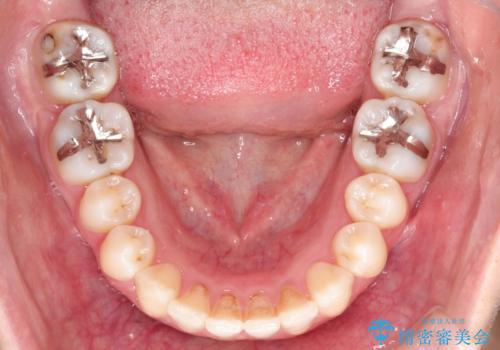

- 前歯の正中離開の改善を希望され来院された患者様です。

初診時の歯並びの状態としては、上下ともに前歯部の中等度のがたつきがあり、特に左上の前歯が1本内側に入り込んでしまっている状態でした。

また、2mm程度の正中離開がありました。

見た目、嚙み合わせ及び、治療期間や施術内容に大変ご満足いただきました。